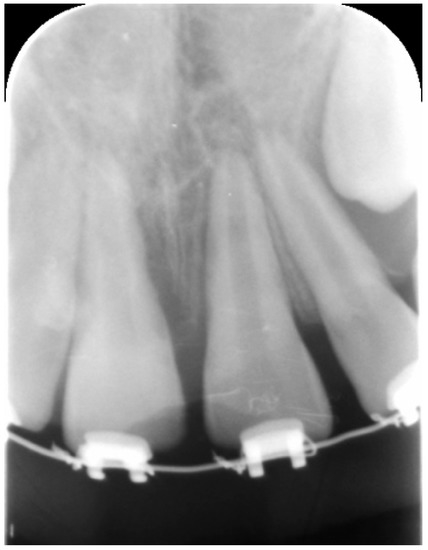

External Root Resorption Management of an Avulsed and Reimplanted Central Incisor: A Case Report

2. Case Report